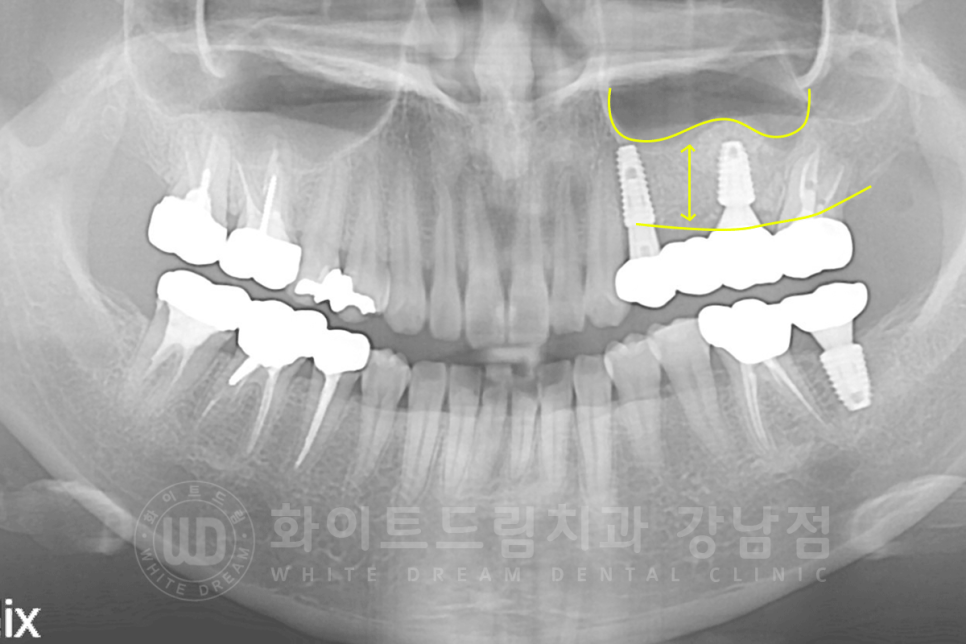

3D-CT를 이용하여 확인하니 잇몸뼈의 두께가 임플란트를 식립하기에는 많이 모자란 상태였기에

상악동 거상술(Lateral)을 진행하기로 했습니다.

▲ 6개월의 회복 기간 후 보철 제작에 들어갔고 최종 보철 세팅 후 x-ray입니다.

수술 전과 후의 잇몸뼈 두께를 보면 차이점이 한눈에 확인되실 겁니다. ^^

동일 인물이며, 동일 환경에서 촬영되었습니다.

치료 기간 : 16.10.25 - 17.05.19